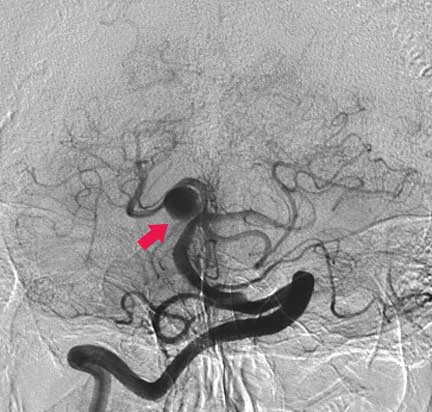

CASO 1 : Embolización endovascular de aneurismas con microespiras (coils) en paciente anciano y de alto riesgo para cirugía abierta

Angiografía antes de la embolización

Angiografía después de laembolización la cual muestra cierre completo del aneurisma